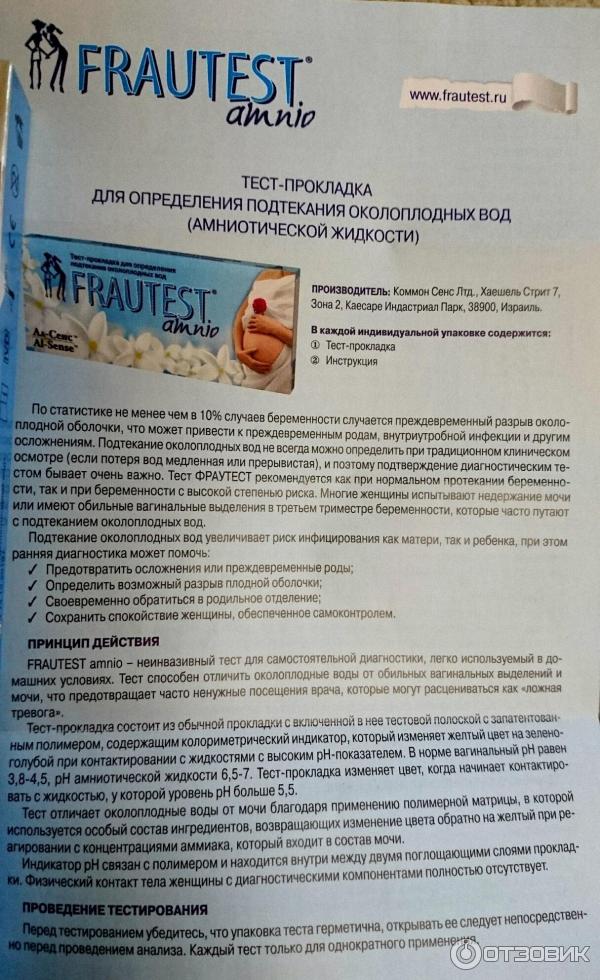

Амнион и Околоплодные Воды: Функции и Роль в Беременности